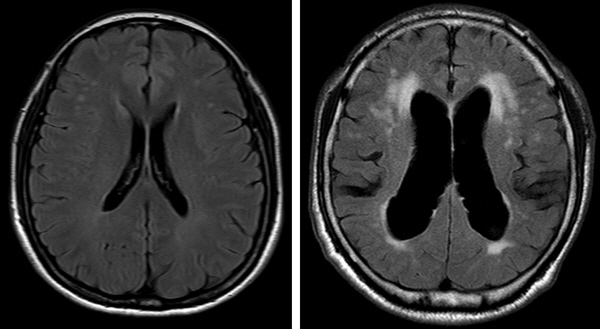

뇌척수액은 뇌실에 존재하는 맥락총이라는 부분에서 생성되어 뇌 주변을 순환한 뒤 거미막 융모에서 흡수 되는데, 생성이 과다하거나 흡수가 잘 되지 않으면 뇌실 내 적정양인 120~150㎖를 유지하지 못하고 점점 축적된다. 이러한 상태를 수두증이라고 부른다. 그리고 뇌척수액의 압력이 정상 범위인데도 수두증이 나타나는 것을 정상압 수두증이라고 한다. 이렇게 과다 축적된 뇌척수액이 뇌 조직을 압박하게 되면 보행·배뇨장애, 기억저하와 같은 증상으로 나타나는 것이다. 단순히 증상만 놓고 보았을 때는 파킨슨병으로 오인하기 쉽다.